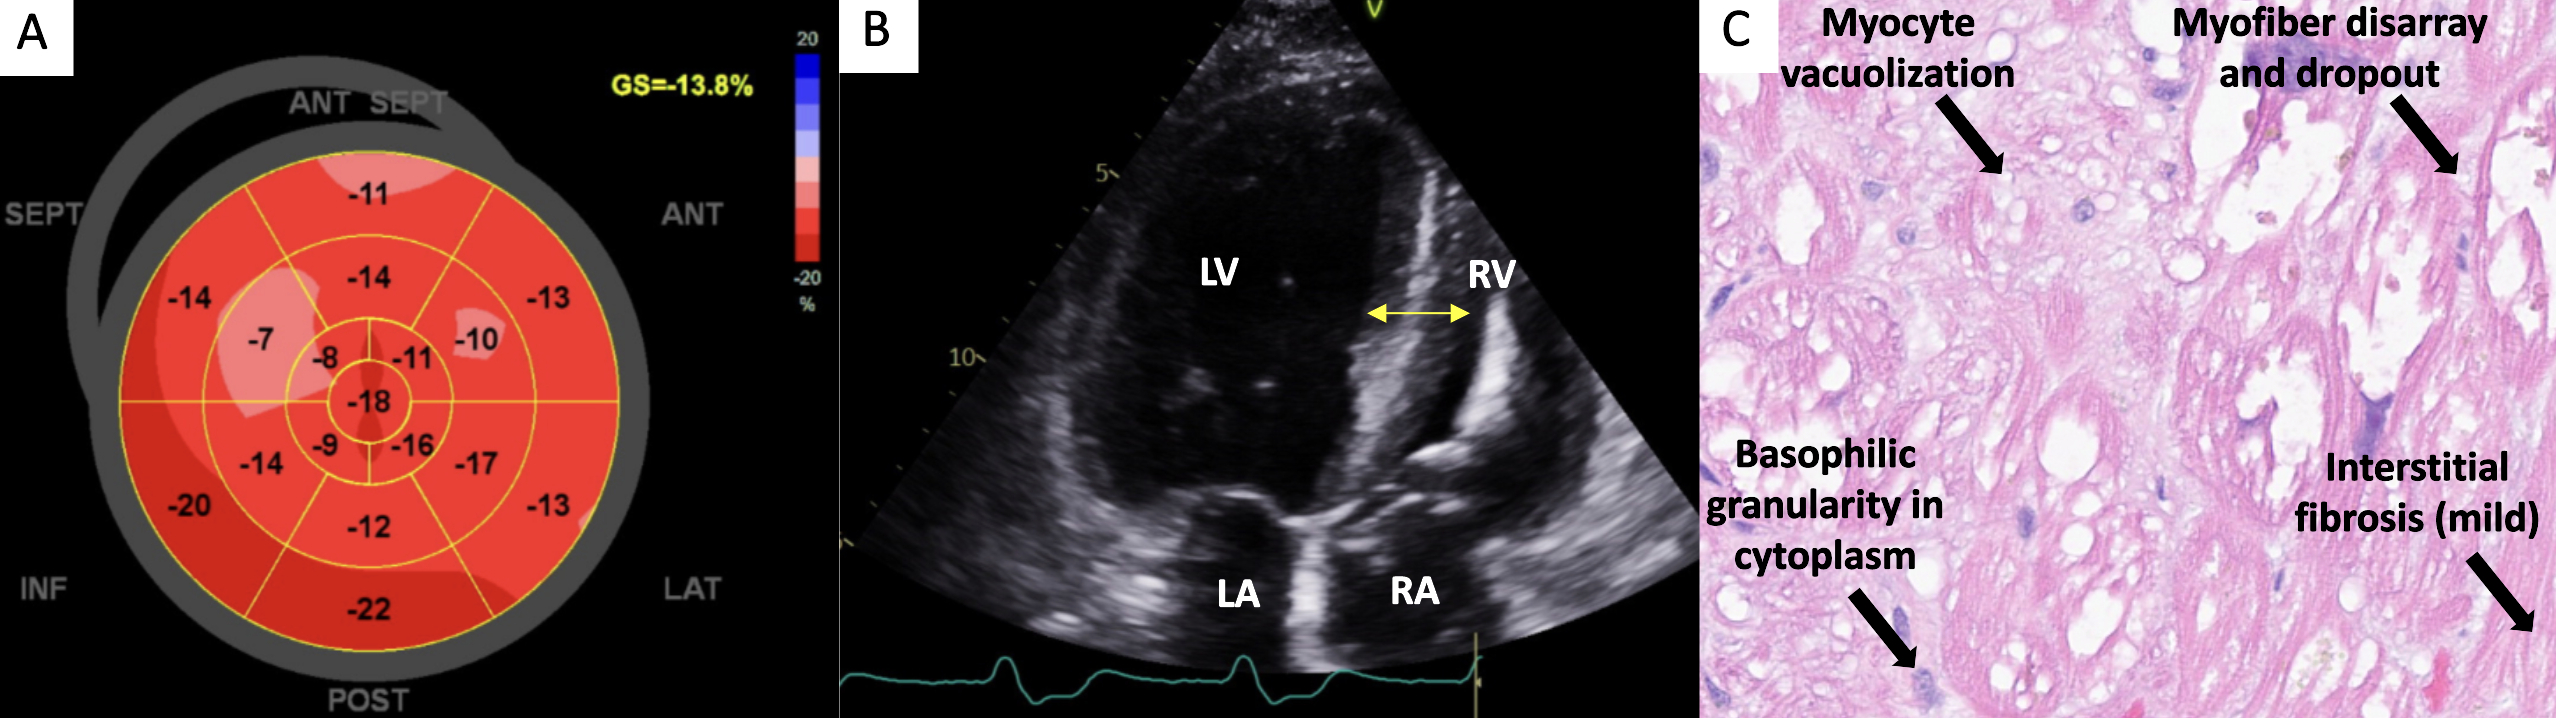

Laboratory evaluation was notable for NT pro-BNP > 5000 pg/mL and elevated but adynamic troponin (300-500 ng/L). Electrocardiogram revealed atrial pacing with first degree atrioventricular block. Echocardiogram confirmed severe aortic stenosis, elevated filling pressures, abnormal left ventricular longitudinal strain and LV hypertrophy. Cardiac MRI, sarcoid PET, and PYP SPECT/CT were without any evidence of edema, scar, inflammation or amyloid deposition. Catheterization revealed severe pulmonary hypertension and elevated filling pressures, without significant coronary disease.

Medical treatment included empagliflozin (discontinued due to urosepsis), bumetanide, spironolactone, and metoprolol succinate. Neither TAVR nor transition to biventricular pacing improved LV function. Ultimately, endomyocardial biopsy was performed, revealing histologic features of HCQ-induced cardiotoxicity, including myocyte hypertrophy and interstitial fibrosis. HCQ was discontinued. She was referred to Rheumatology for alternative treatments.

HCQ induced cardiomyopathy represents <2% of adverse events of patients treated with HCQ, presenting as hypertrophic or restrictive cardiomyopathy with conduction abnormalities. Mean treatment duration in HCQ cardiomyopathies is approximately 12.7 years. Confirmation of diagnosis requires endomyocardial biopsy, as imaging findings are often non-specific. Management involves discontinuing the offending agent and optimizing heart failure therapy. Around 45% of patients with HCQ cardiomyopathy exhibit resolution of cardiac function following medication discontinuation.